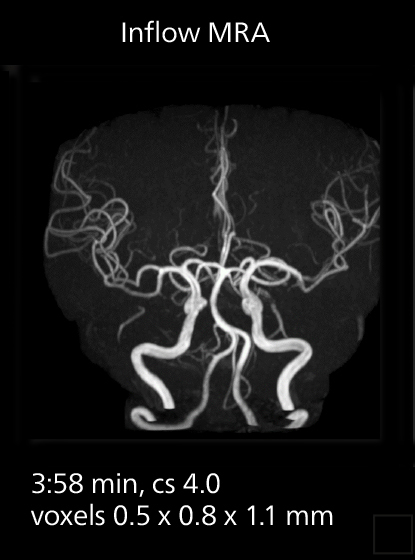

Lumbar spine MRI

Crisp images are obtained with high resolution and short scan times using Elition X. A cyst can be seen.

Lumbar spine MRI

Crisp images are obtained with high resolution and short scan times using Elition X. A cyst can be seen.